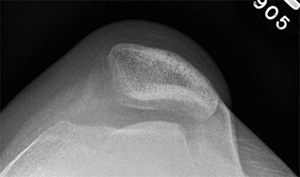

Because of the limitations of physical exam alone, imaging is also used to assist in making a diagnosis; a lateral plain film can show three common signs of trochlear dysplasia: presence of a supratrochlear spur, crossing sign and double contour sign. Taken together these findings allow for classification according to the Dejour system [7]. A standard knee series of plain radiographs (x-rays) will show if there is a fracture of the patella or if there are other malalignment which may contribute to patellar instability or recurrent instability. Other important studies include a magnetic resonance image (MRI). This is typically ordered after an initial dislocation to ensure that there is not a cartilage fracture which could potentially be repaired. Furthermore, early MRI will show damage to the tissues that may be more difficult to see once swelling and inflammation recede. Computed tomography (CT or CAT scan) is not usually required for diagnosis, but can be obtained to confirm the type of dysplasia into one of four Dejour categories and perform other measurements which are useful in preoperative planning for reconstruction once the decision for surgery has been made [7]. Measurements of valgus alignment, sulcus angle, and tibial tubercle-trochlear groove distance help determine what type of corrective procedure is required and what degree of correction is needed.